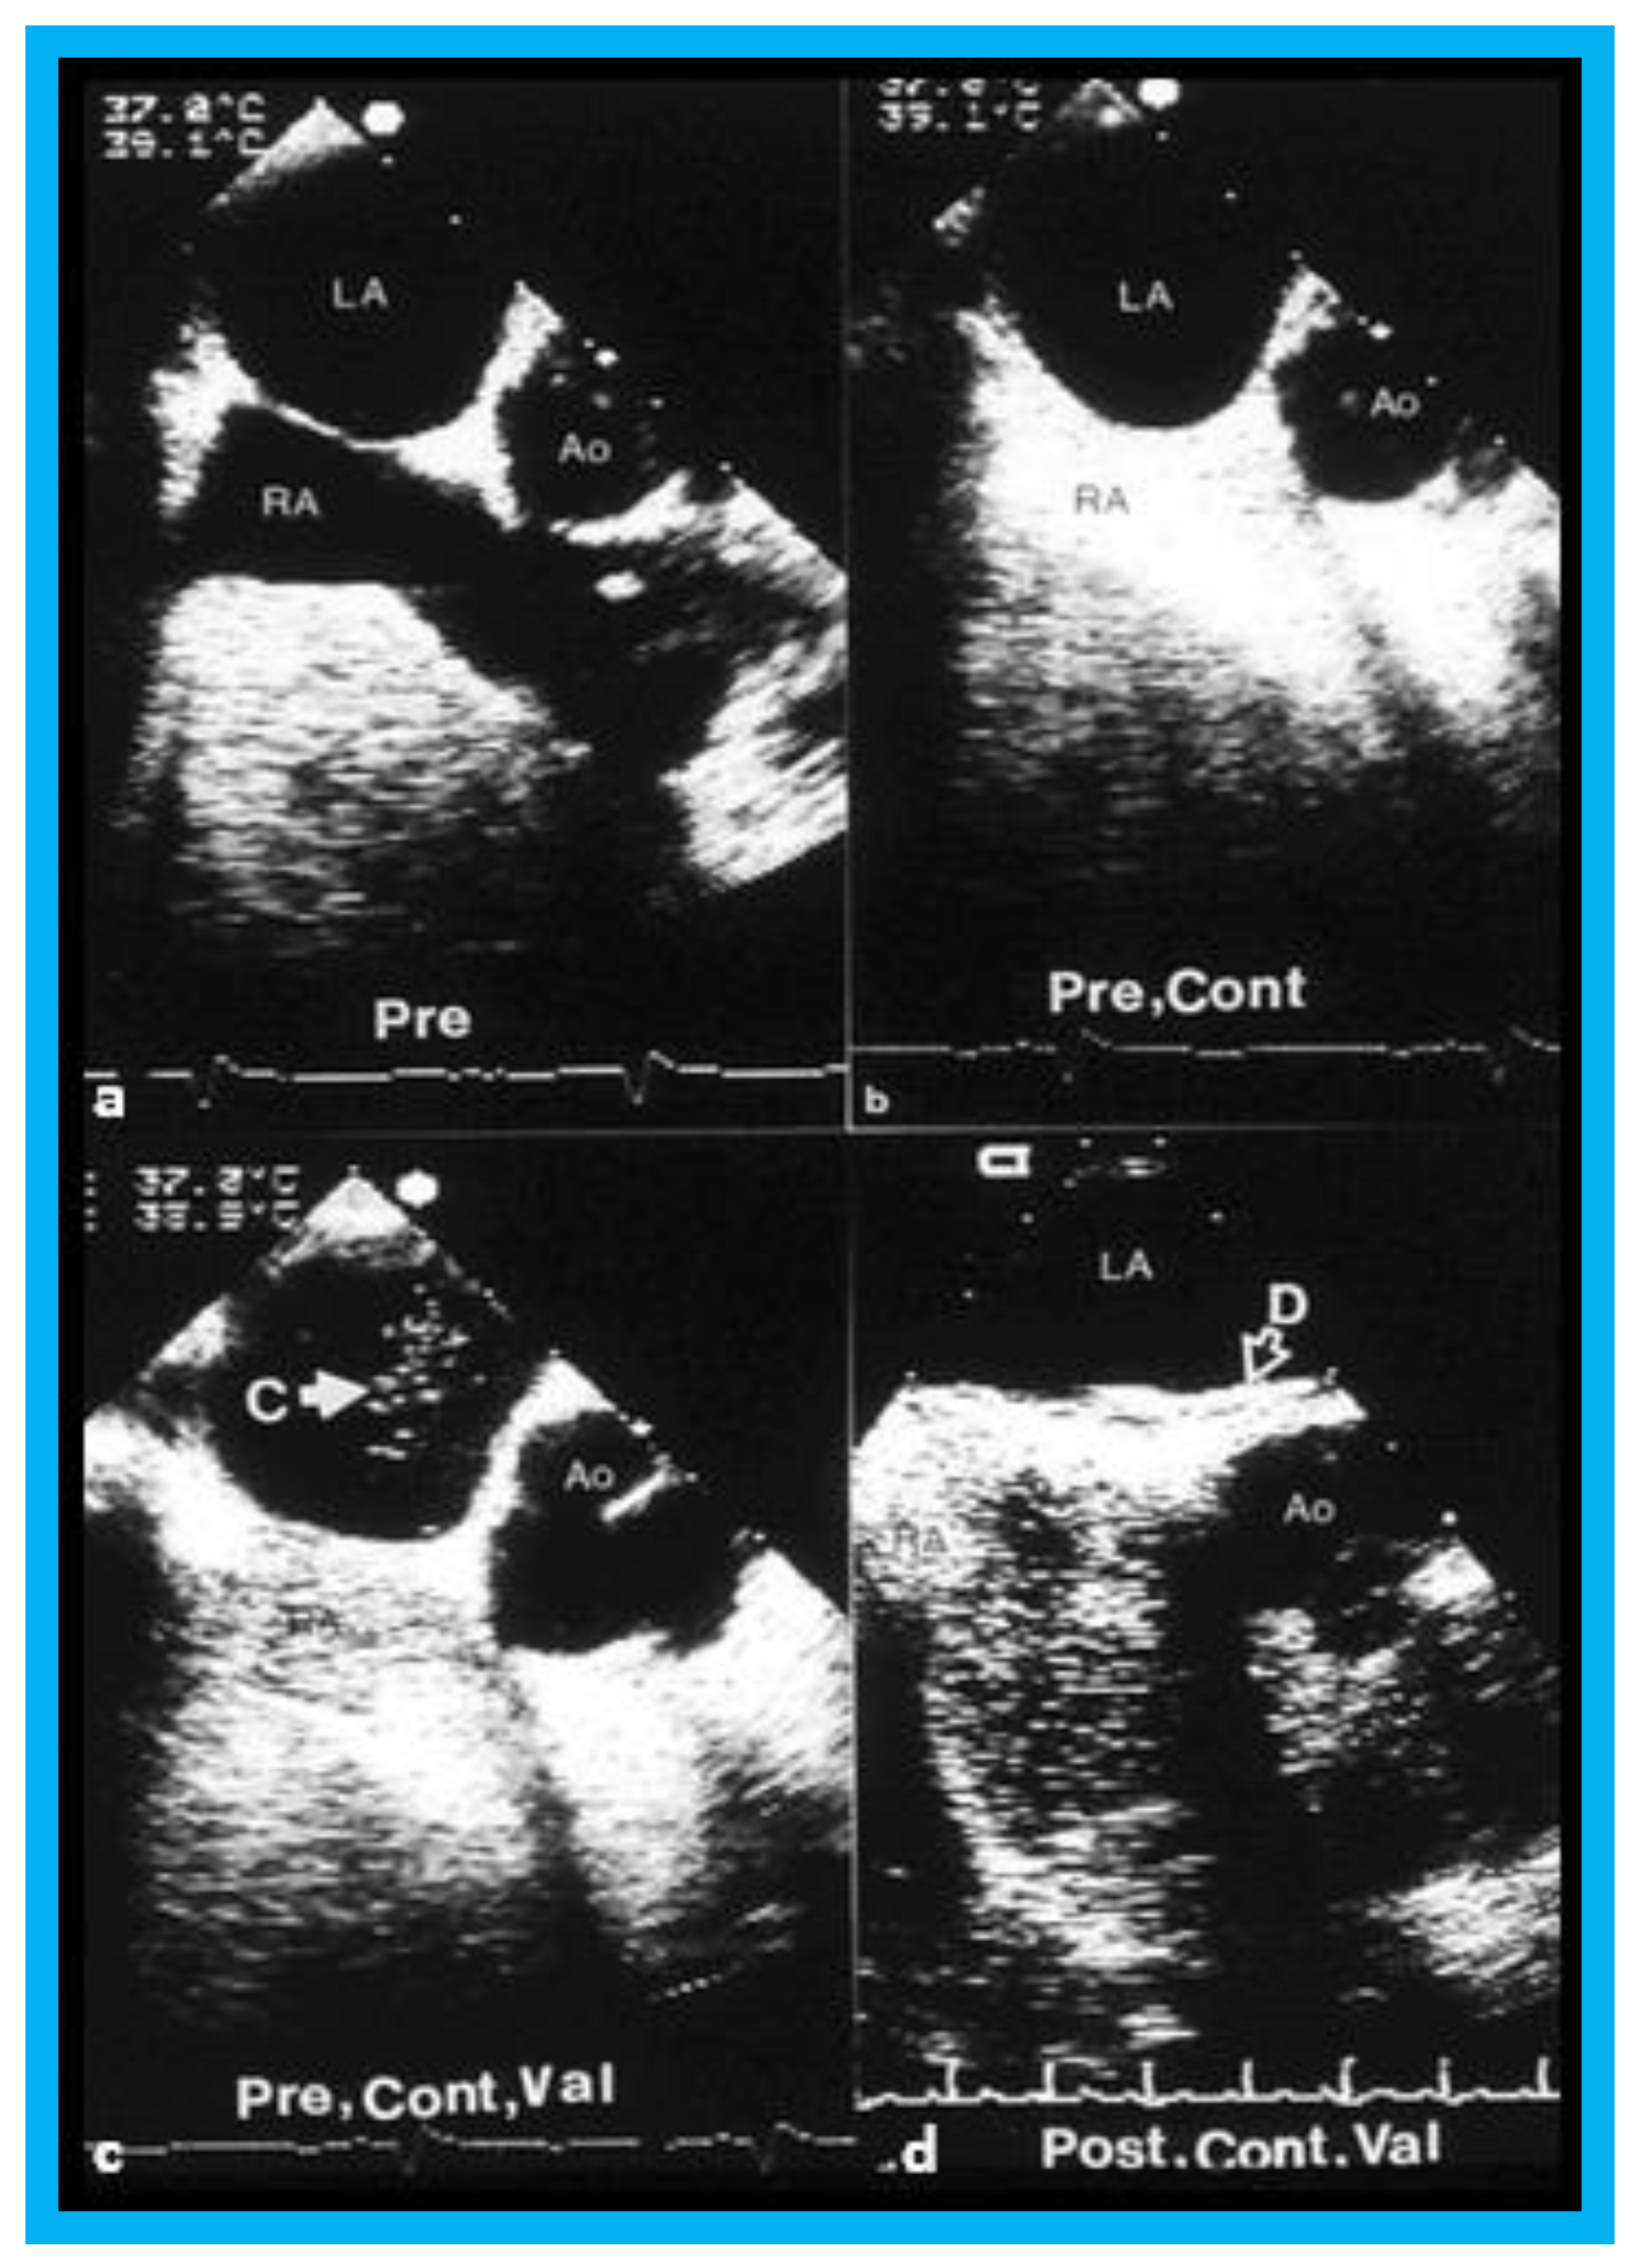

In group II (5 adult patients, aged 36 to 51 years, with presumed paradoxical embolism), on repeat transesophageal contrast echo study with Valsalva, minimal right-to-left shunt was seen initially (3 months) in two of five patients (40%), which completely disappeared at further follow-up (Figure 11). No patient developed cerebrovascular accident (CVA) or transient ischemic attack (TIA) during a 18-to-43-month follow-up.

Figure 11. Selected video frames from transesophageal echocardiograms in an adult with presumed paradoxical embolism prior to (Pre) (ac) and six months (post) (d) after closure of patent foramen ovale with buttoned device: Short axis views illustrate aorta (Ao) in the middle and right atrium (RA) and left atrium (LA) to the right before (a) and after (b) injection of agitated saline into the RA. Note that there are no contrast bubbles in (b). However, with contrast and Valsalva (Val) (c), the LA is opacified (C filled arrow). Study similar to c, performed six months following (d) (post, Cont, and Val) shows the device (unfilled arrow D) without contrast bubbles in LA. Note that contrast bubbles are seen in RA in (bd). Reproduced from Rao P.S., et al. [9].